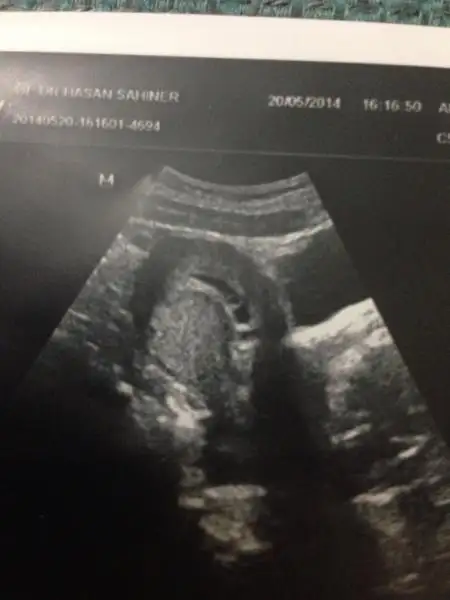

bak seklı boyle bıldıgın sıvrı bıber hemen yanında top gıbı bır kese var hatta o daha duzgun ama o ıkıncı bır kesemı yoksa kanamam lekelenmem var dıye olusmus bır pıhtı mı orası bellı deılEki Görüntüle 1209564

bak ilk öğrendiğimde yani 5haftalıkken Eki Görüntüle 1209475 Buda 7 hafta yolk sac kesesi yuvarlak olan. Eki Görüntüle 1209481

bak ilk öğrendiğimde yani 5haftalıkken Buda 7 hafta yolk sac kesesi yuvarlak olan.